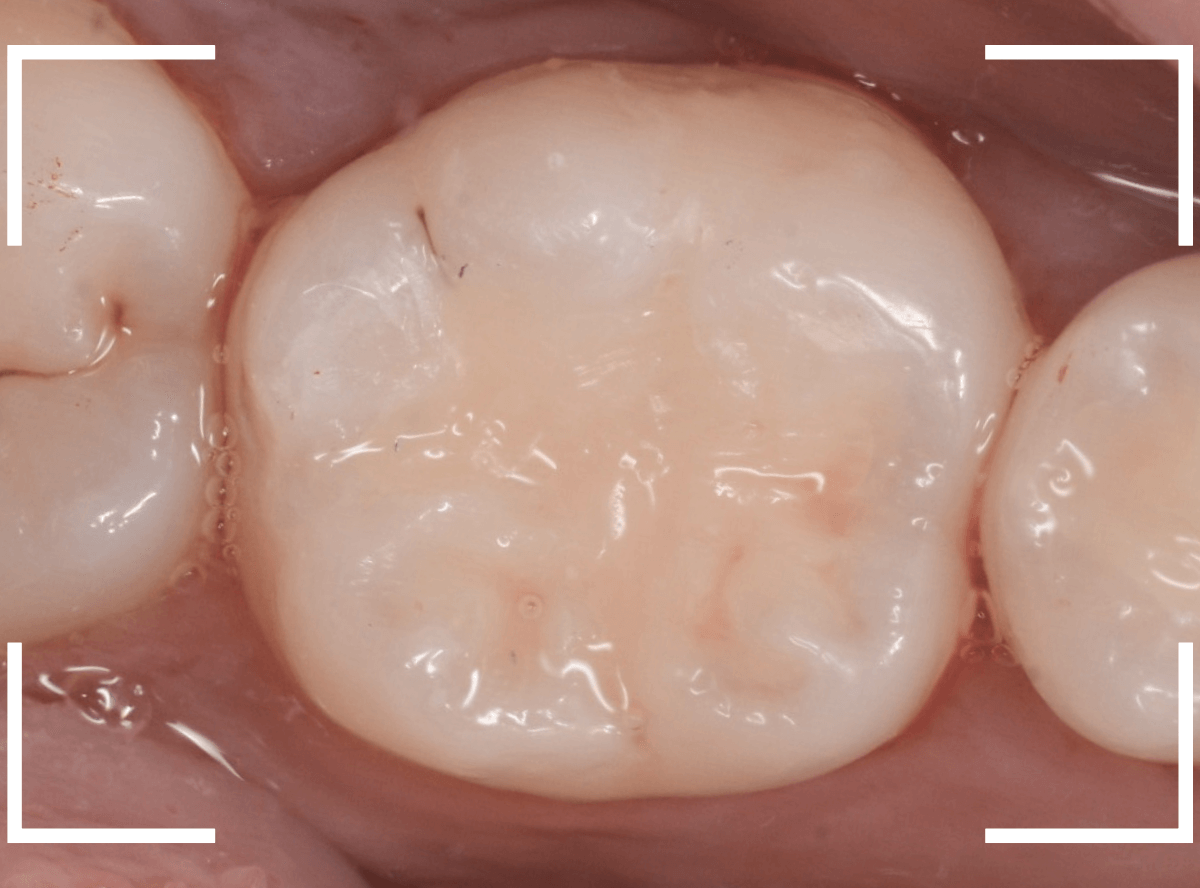

Case.7 レントゲンに写らないレジンの中の虫歯を削って調べる

こちらも定期検診希望で来院された患者さんです。

特に症状はありませんが、歯の咬頭(噛み合わせの山の部分)に小さな穴が空いていて、その周りがもやっと黒く見え、虫歯が怪しいです。

レントゲン写真で確認しますが、ここでは特に問題はなさそうに見えます。

患者さんに状況を説明し、慎重に削って調べる事になりました。

少しずつ穴の部分を削ってみると、ズブッと落とし穴にはまるような柔らかい虫歯の層(=軟化象牙質)に当たりました。

慎重に虫歯を除去したところです。

歯の溝のレジンが詰めてあった部分まで虫歯は進行していました。

とはいえ、それほど深く虫歯は進行していませんでしたので、虫歯除去後、レジンを充填して治療は終われました。

このように定期的にメンテナンスに来ていただくと虫歯が本格的に進行する前に対処する事ができます。